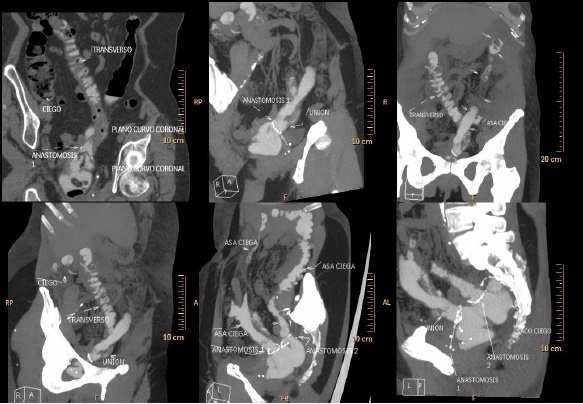

Se encontraron cambios postquirúrgicos en recto medio los cuales están dados por la presencia de doble anastomosis. Una de ellas es funcional (constituye el trayecto principal del contenido intestinal), está localizada en la pared anterior del recto y conecta con el colon derecho, ángulo hepático y el segmento proximal del colon transverso; la otra anastomosis no es funcional y conecta el recto a un circuito cerrado entre el segmento distal y el ángulo esplénico del colon transverso y el colon descendente (Figuras 1, 2 y 3).

Figura 1 Caso1: imágenes tomográficas multiplanares del colon a partir de las cuales se realizó el PPIT. Se observan varias anastomosis entre los segmentos colónicos, la disposición excepcional del colon transverso y áreas con aspecto de asas ciegas en zonas del colon y del recto